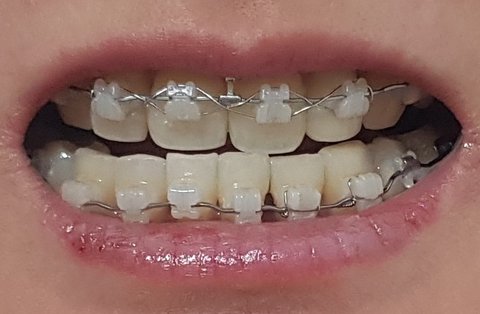

아래는 2021년에 찍은 제 치아 사진입니다.

윗니와 아랫니 모두 수평이며 수직이며 대칭이며 무엇도 맞지 않습니다.

제기준 왼쪽 아랫니 블랙트라이앵글 부분은 6달 전부터 내원 할때마다 처리해달라고 한 부분인데

이리저리 이동시키시더니 3일전 내원했을 때 `처리 못해주겠다, 불가능하다`는 식으로 말씀하시더군요. 말씀만 그리 하시고 다시 또 뭔가 조절은 해주셨는데